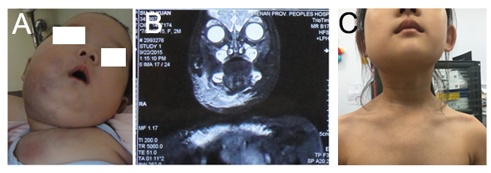

病例1:右面颈、胸壁广泛卡泼西样血管内皮瘤伴KMP,经过治疗后6年随访。

病例1:右肩部、上肢卡泼西样血管内皮瘤伴KMP,经过治疗后6年随访。